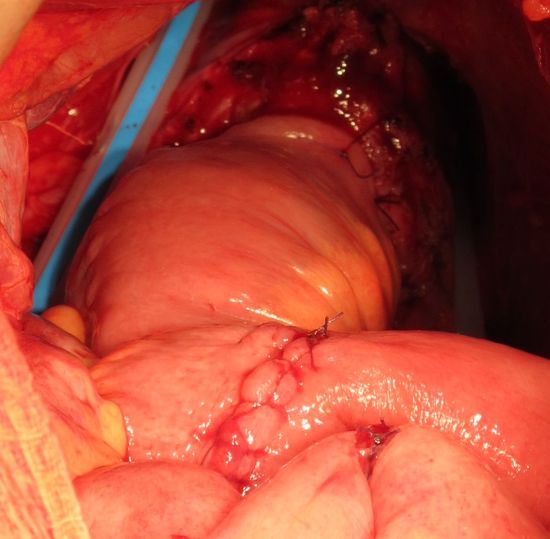

Необладер фиксирован в ортотопической позиции. Малый таз дренирован двумя дренажными трубками.